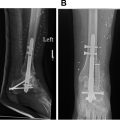

Case demonstrations (up to 4 cases)